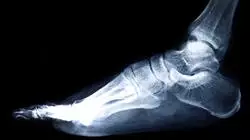

Verranno affrontate le nuove procedure degli esami radiologici in podologia sportiva, nonché le loro posizioni in dettaglio, i meccanismi d'azione radiobiologici, la radioprotezione e l'ecografia muscolo-scheletrica, che sta diventando sempre più importante nella pratica clinica dei podologi, sia nella diagnosi che nel successivo trattamento, rendendo questo programma una risorsa molto pratica per aggiornare le conoscenze del professionista.

L'aumento dell'adozione di pratiche sportive come parte fondamentale della routine settimanale degli individui ha portato a una maggiore domanda di lavoro per i professionisti medici responsabili della cura delle anomalie muscolo-scheletriche, evidenziando in particolare l'ampio campo occupazionale che attualmente esiste per i professionisti della podologia applicata allo sport. Comprendendo questa nicchia di lavoro e le opportunità professionali che genera, in TECH Università Tecnologica abbiamo progettato un eccellente programma di Esperto Universitario in Podologia Sportiva e Ortopodologia, incentrato sull'aggiornamento teorico-pratico dello studente verso le ultime tendenze del settore, coprendo aspetti quali: le nuove possibilità terapeutiche nella cura delle lesioni legate alla fascite plantare e alla metatarsalgia; e le particolarità da tenere in considerazione nella prevenzione di future anomalie derivanti da queste lesioni.

Il nostro Esperto Universitario in Podologia Sportiva e Ortopodologia per la cura degli infortuni sportivi ti darà l'opportunità di accedere a un programma di studi accuratamente progettato da esperti del settore, per garantire ai nostri studenti una specializzazione completa sui fondamenti della podologia. Questo aggiornerà le conoscenze del professionista su aspetti quali: l'utilità della radiobiologia nelle procedure diagnostiche in ortopedia; gli ultimi progressi nella produzione di supporti plantari e altre tecniche ortopediche nel campo dello sport.